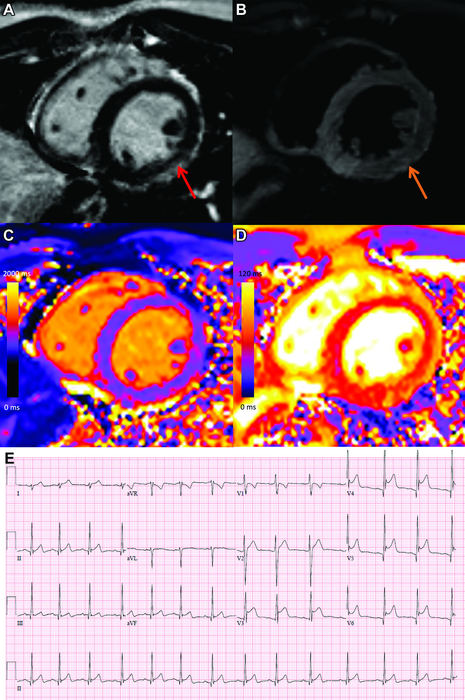

OAK BROOK, Ill. (February 15, 2022) – Vaccine-associated myocarditis shows a similar injury pattern on cardiac MRI compared to other causes of myocarditis, but abnormalities are less severe, according to a new study published in the journal Radiology.

Cardiac MRI has an important role in the assessment of acute myocarditis with unparalleled ability for noninvasive characterization of myocardial tissue. Understanding the pattern and extent of myocardial injury and its implications will allow for improved care of these patients and may help to address vaccine hesitancy.

MRI findings in vaccine associated myocarditis included late gadolinium enhancement in 17 (81%) and left ventricular dysfunction in 6 (29%). Cardiac MRI showed that, compared with other causes of myocarditis, patients with vaccine-associated myocarditis had less functional impairment and less extensive myocardial abnormalities. Patients with COVID-19 illness and other myocarditis had a higher prevalence of abnormalities involving the interventricular septum and worse myocardial injury measured by T1 mapping.